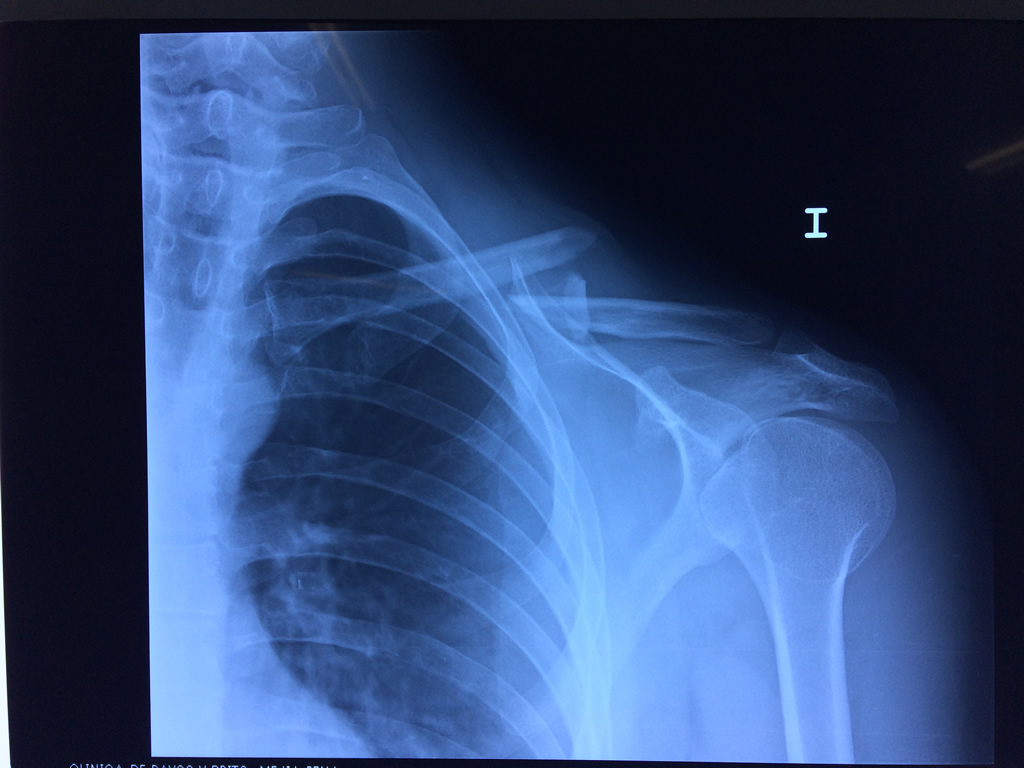

Cirugias en El Salvador - Clavícula

La clavícula es un hueso largo, con forma de "S" itálica, situado en la parte anterosuperior del tórax. Junto con la escápula forman la cintura escapular. Se puede palpar por toda su longitud y se extiende del esternón al acromion de la escápula, siguiendo una dirección oblicua lateral y posterior.